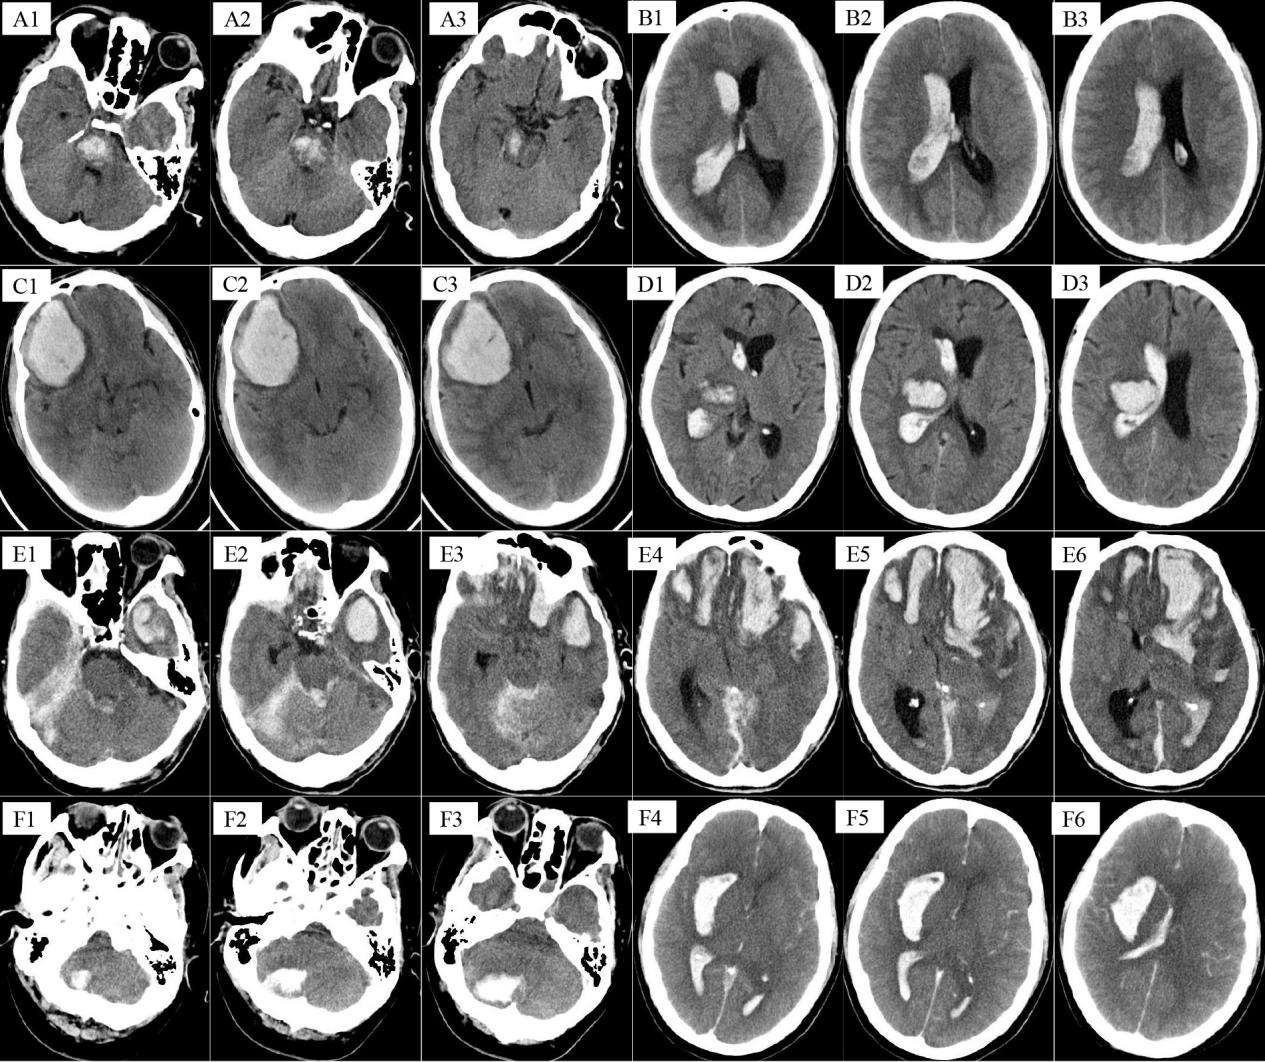

As shown in Figure 1, during the acute onset of cerebral hemorrhage, hemorrhage developed in the brain lobe solely (n=5), basal ganglia (n=2), ventricle (n=2), subdural (n=4), subarachnoid hemorrhage (n=3), brainstem (n=1). The most common symptoms were headache, which occurred in 12 (57.1%) patients, and the other symptoms were coma in 4 (19%), epilepsy in 1 (4.8%), fatigue in 2 (9.5%), vomiting in 2 (9.5%), and dizziness in 1 (4.8%) patient. Only 2 patients accepted surgery, among which, and one patient chose automatic discharge final while the other recovered well and discharged successfully. 4 (19%) patients developed cerebral hemorrhage in multiple parts, which caused poor prognosis. The average hematoma volume was 17.8ml (range:4-80ml; Table 2). It was worth to mention that GCS score in most patients were not below 8. At the same time, GOS score in most patients were 4 and above (Table 2).

A1-A3 were obtained from a 31-years-old male who had no traditional vascular risk factors, but developed cerebral hemorrhage (a lesion in the brainstem) at 20 years after diagnosis of hemophilia. B1-B3 were obtain from a 50-years-old male who had no traditional vascular risk factors, but developed cerebral hemorrhage (a lesion in the right paracele) at 10 years after diagnosis of hemophilia. C1-C3 were obtain from a 34-years-old male who had no traditional vascular risk factors, but developed cerebral hemorrhage (a lesion in the right frontal lobe) at 26 years after diagnosis of hemophilia. D1-D3 were obtain from a 59-years-old male who had no traditional vascular risk factors, but developed cerebral hemorrhage (a lesion in the right basal ganglia) at 35 years after diagnosis of hemophilia. E1-E6 was obtained from an 85-years-old male who had hypertension and diabetes for more than 20 years. There was a history of head trauma which caused cerebral hemorrhage in bilateral frontal lobe, left temporal lobe, ventricle and subdural. F1-F6 was obtained from a 41-years-old male who had hypertension for more than 10 years and developed a lesion in the right cerebellum, right basal ganglia and ventricle.